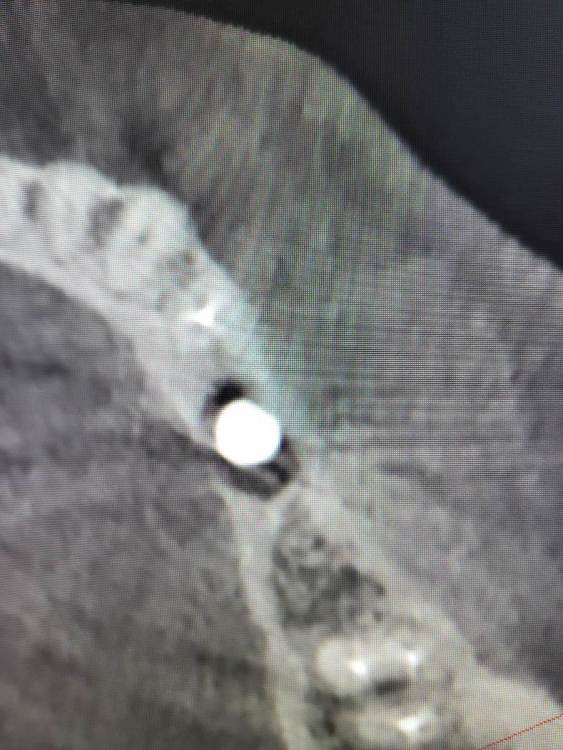

Irouil Опубликовано 28 ноября, 2023 Поделиться Опубликовано 28 ноября, 2023 Дорогие коллеги, прошу советов и мнений Пациентка 52 лет, соматика без особенностей В мае 2023 установлен имплант в позицию 3.5, первый срез КТ - на момент установки. В августе был утерян ФДМ, установил другой, снимок на момент обращения с незначительной резорбцией В ноябре пациентка пришла протезироваться, у винта выраженная щелевидная резорбция язычно и кратерообразная - параплатформенно Три других винта, установленных в то же время (но без головняка с ФДМ) выглядят более чем удовлетворительно Что скажете? P.S. поперечный срез КТ выставлен на уровне платформы импланта Ссылка на комментарий

АнтонТЛТ Опубликовано 28 ноября, 2023 Поделиться Опубликовано 28 ноября, 2023 Фдм упёрся в кость язычно, кость от сдавления рассосались, фдм расшатался и начал подсасывать слюну. А потом совсем выпал. 1 3 Ссылка на комментарий

Irouil Опубликовано 28 ноября, 2023 Автор Поделиться Опубликовано 28 ноября, 2023 29 минут назад, АнтонТЛТ сказал: Фдм упёрся в кость язычно, кость от сдавления рассосались, фдм расшатался и начал подсасывать слюну. А потом совсем выпал. Все так, но вопрос не в этом Вопрос в том, почему резорбция усилилась после установки ФДМ и какой выбрать план действий? Я периодически наблюдаю реминерализацию тканей в таких дефектах после фиксации протетики, но только на конусах. С другой стороны, глубокий дефект здесь достаточно узкий и только в одном месте, окружён хорошими стенками. Не хочу проводить имплантопластику (по мне уже проще переустановить, если винт не запротезирован), но надкостнично думаю провести небольшой кюретаж (по краям костных стенок дефекта), поменять ФДМ на новый и дать время. P.S. есть ещё снимок сразу после рефиксации ФДМ, там картина в разы лучше (собственно, он сделан в тот же день, что и снимок без ФДМ) Ссылка на комментарий